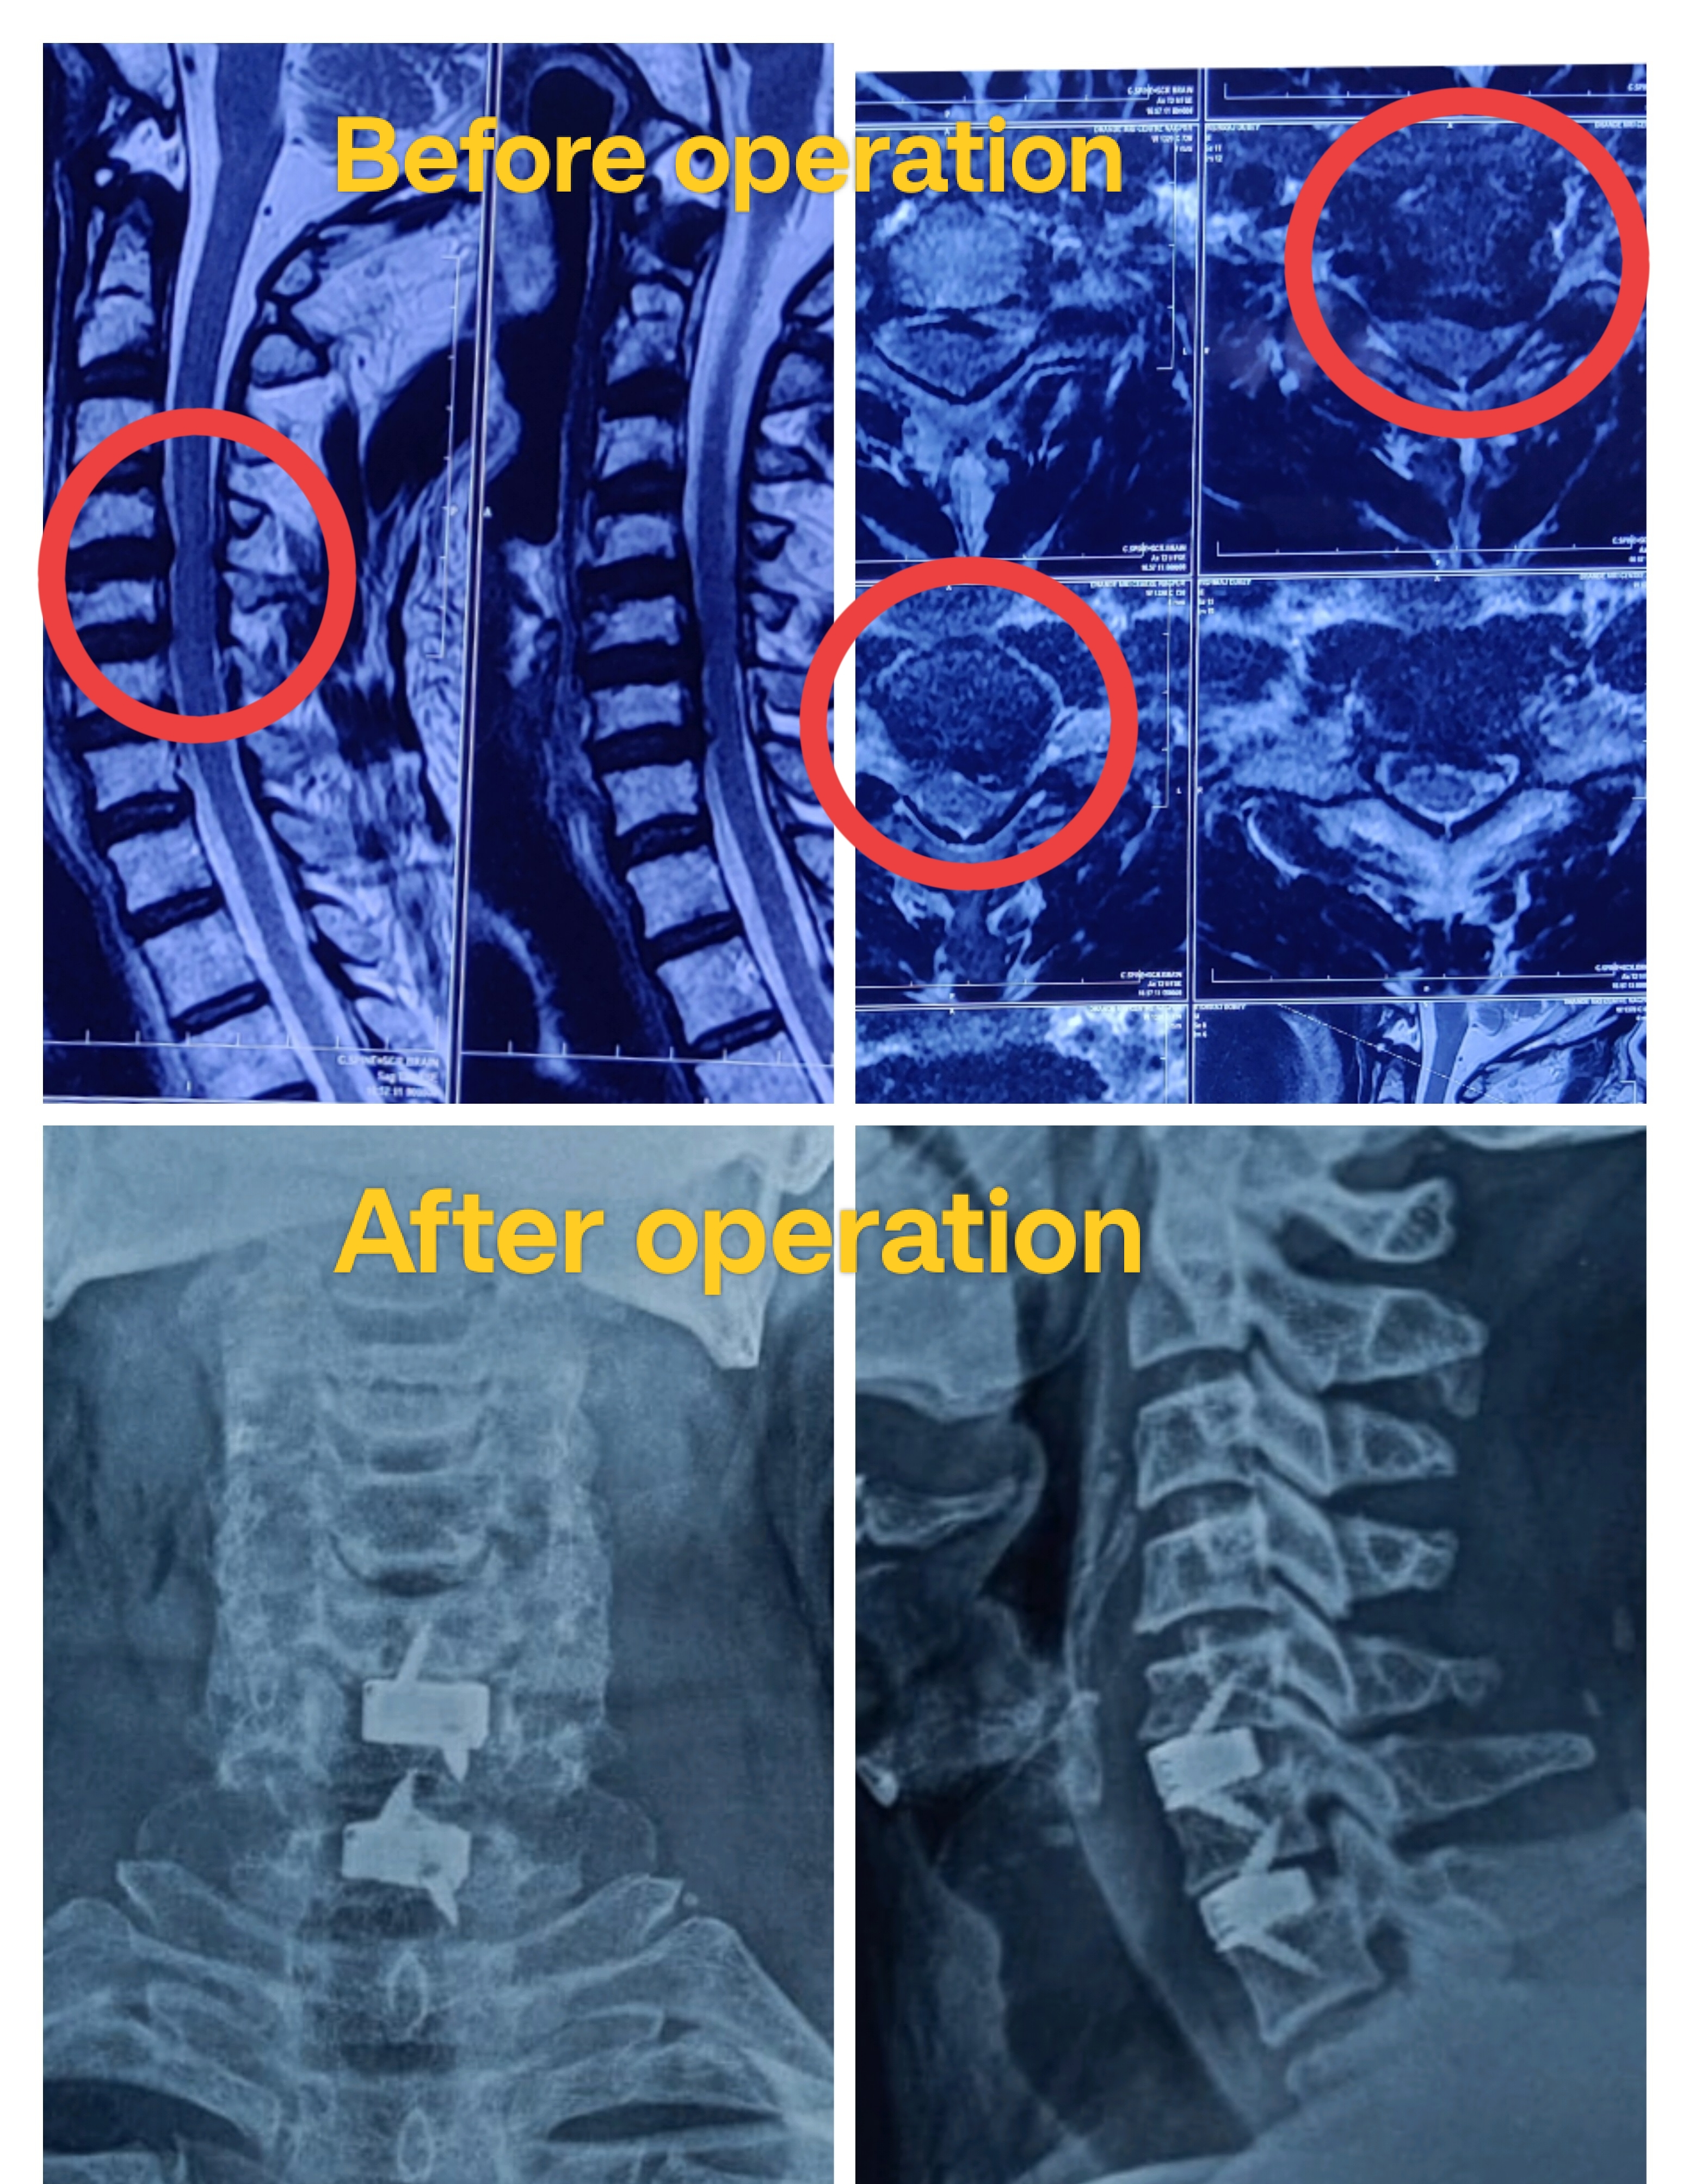

४५ वर्ष पेशेंट जिनकी गर्दन की नस में दो जगह दबाव के कारण हाथ में कमजोरी आ गई थी। इनका सफल ऑपरेशन Dr.Nikhil Kakani sir द्वारा किया गया। पेशेंट अभी स्वस्थ है और हाथो की ताकत मे सुधार आ गया है। #CervicaldiscOperatedsuccesfully #BraininjurySpineinjury #CervicalLumbarPIVDSciatica #DrNikhilKakaniTopmostNeurosurgeonNagpur #NeuroandSpineCareCentre #ExcellentBrainandSpinesurgeon #BestNeurologistNeurosciencesRamdaspethDhantoliLokmatchowkWardharoad #BestNeurophysicianatManishnagarBesaPiplaBeltarodiNearme